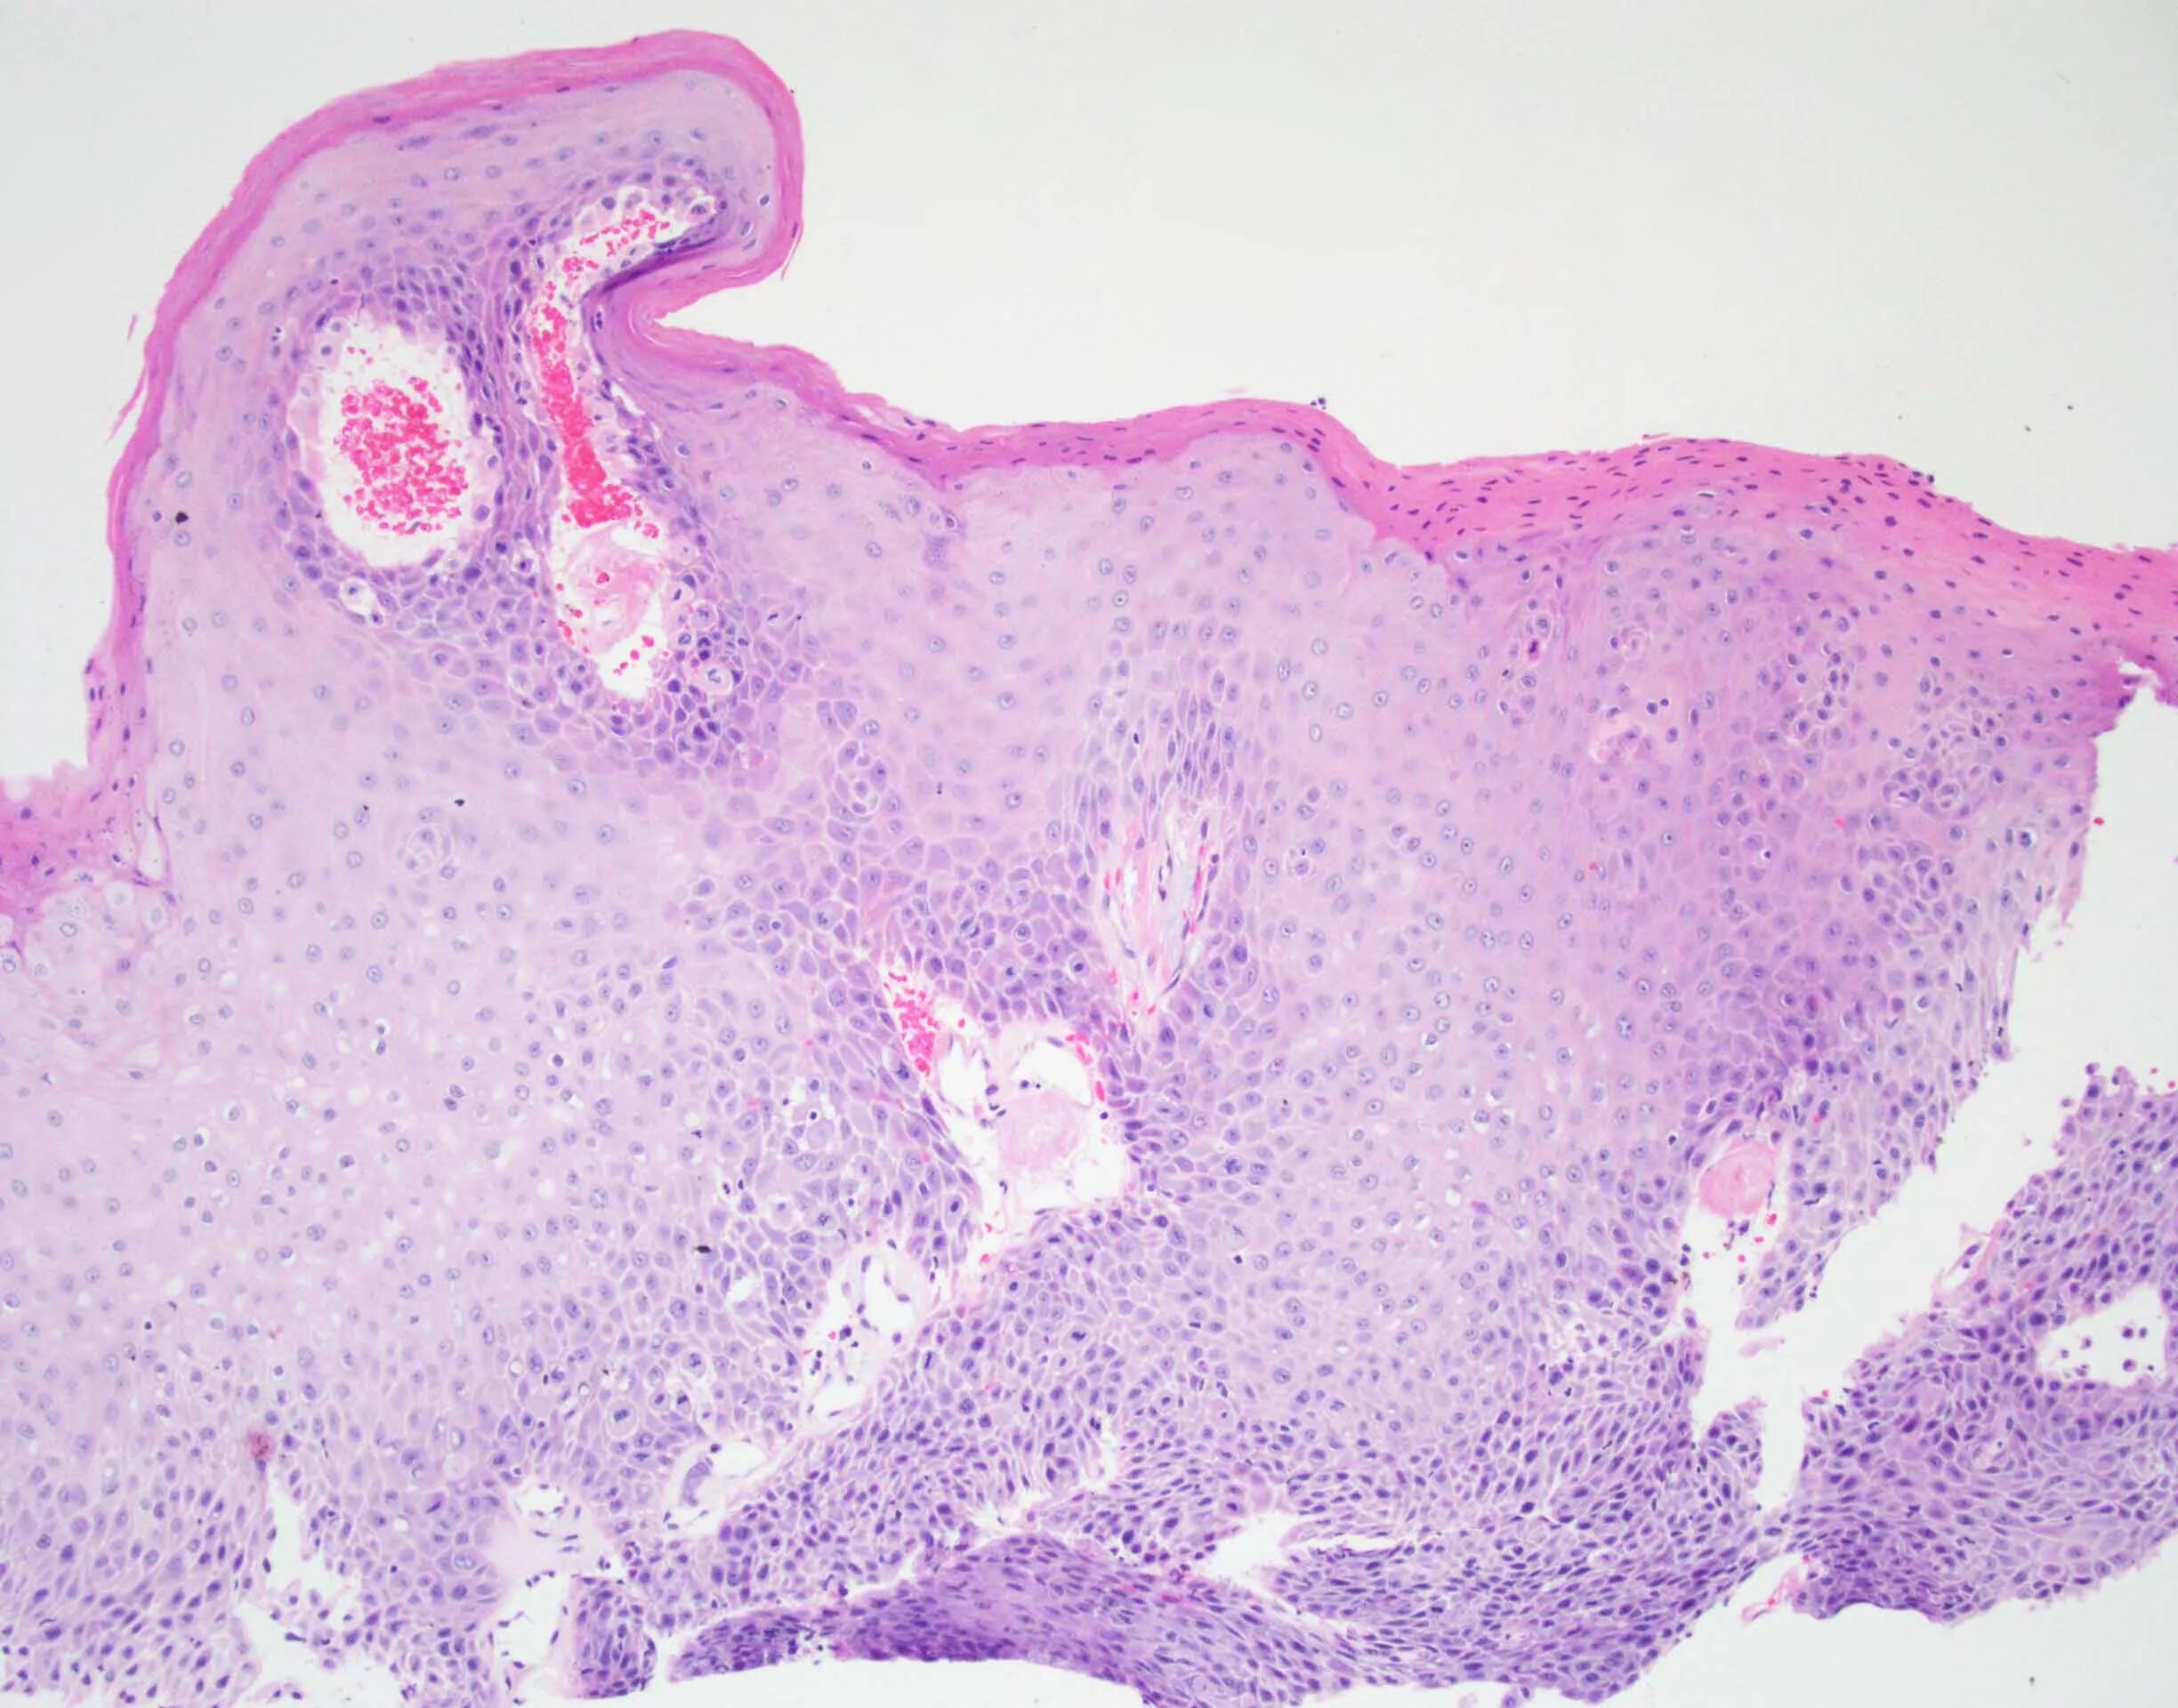

Папиллома гистология